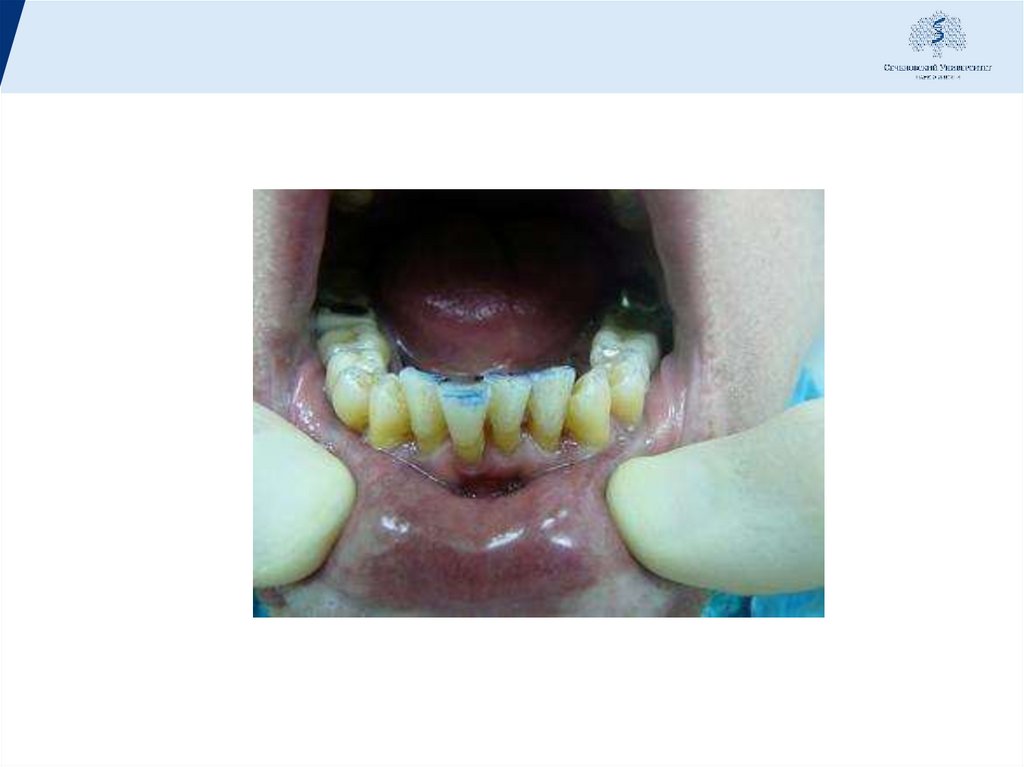

43. Технология наложения шины:

1.Предварительная абразивная обработка поверхности зубов для создания ретенционных пунктов.

2.Протравливание поверхности зубов.

3.Нанесение бонда на поверхность зубов.

4.Поэтапное прикладывание ленты к зубному ряду с заведением в межзубной промежуток и

засвечиванием поверхности.

5.В завершение шина покрывается тонким слоем композита с последующей полировкой. При

изготовлении шины, из гигиенических соображений, необходимо оставлять открытыми

придесенные промежутки между зубами.